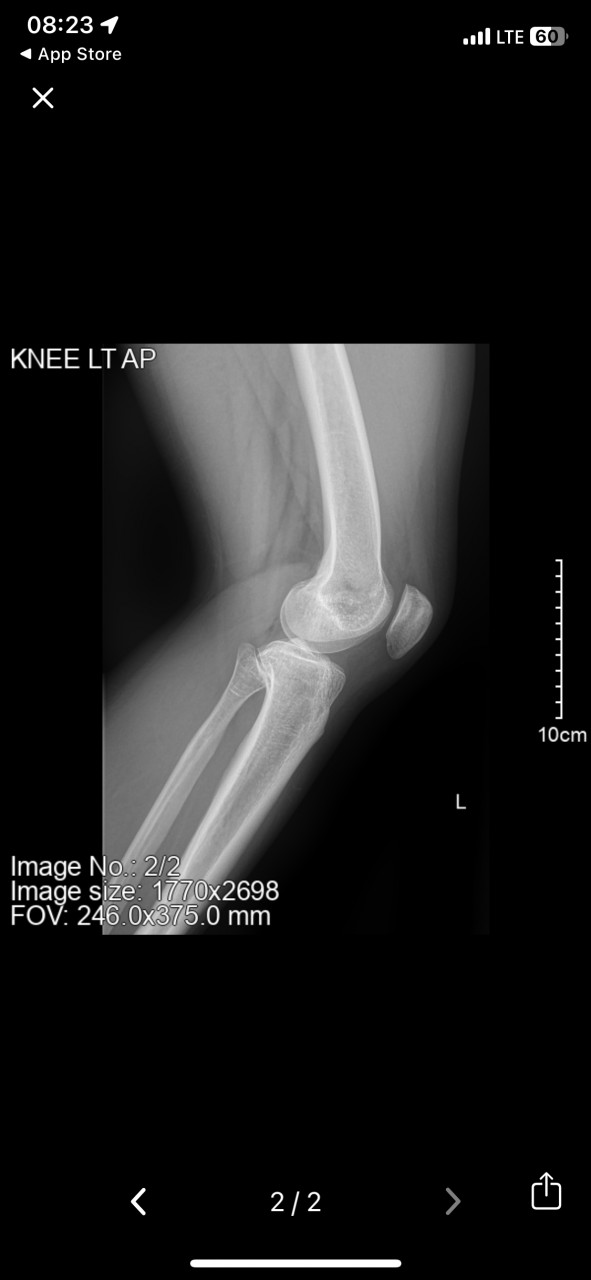

Заключение Очаговое структурное изменение наружного мыщелка левой большеберцовой кости.

Здравствуйте. На рентгене видно очаговое изменение в наружном мыщелке большеберцовой кости  это может быть следствием нагрузки, травмы или дегенеративного процесса. Наличие или отсутствие отёка по снимку не определить т.к отёк оценивается при осмотре, пальпации или с помощью УЗИ,МРТ.

Если есть отёк и боль, временно можно применять нестероидные противовоспалительные мази (например Диклофенак, Фастум-гель), но лучше уточнить диагноз очно при осмотре.